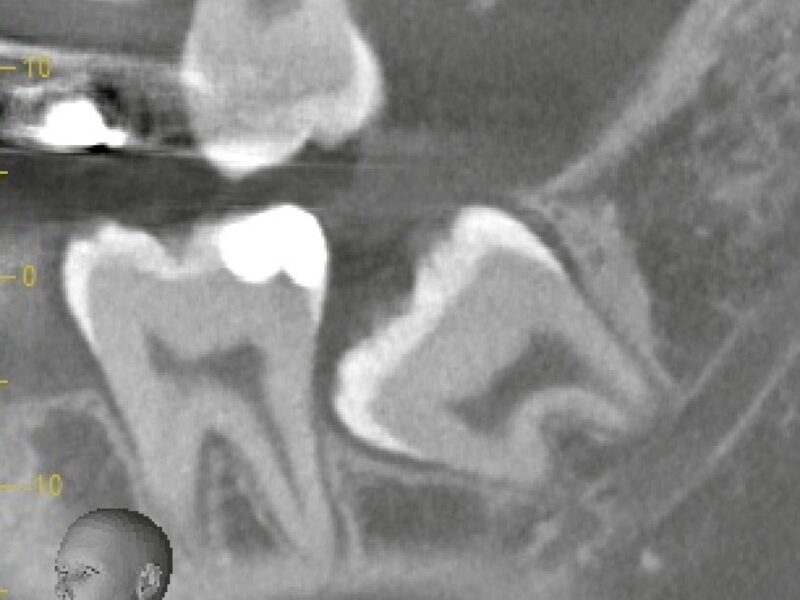

特徴4高精度診断を可能にする「歯科用CT」 -